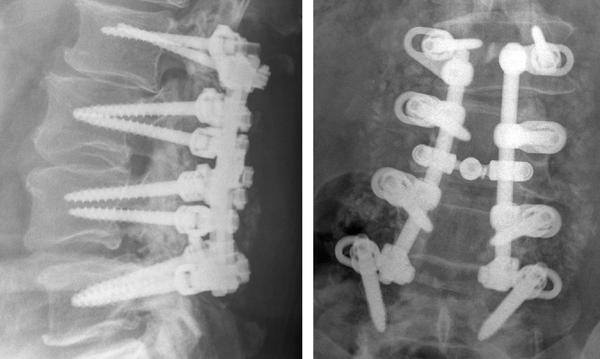

Many of you have asked for an update regarding my back since the surgery 2 1/2 years ago, and want to know how to pray. Thank you so very much!! These pictures show the location of the titanium fusions that were performed.

up, they will turn me over and open up my back and remove everything that you see in these pictures. They will reinstall new hardware and fuse another vertebrae above these. When that is closed up, they’re going to come in from the side and break the bone that has been growing for these 2 1/2 years that has strengthened the titanium. They need to do this in order to insert wedges between my vertebrae to force a proper lumbar curve.